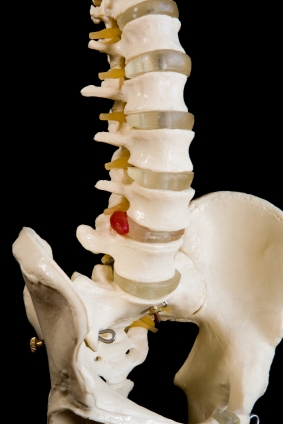

Также называется грыжи межпозвоночного диска или поврежденных дисков. Позвоночник состоит из костей (позвонков), разделенных желатиновых подушки (диски). Диски удерживается на месте с связок. Когда эти связки слезу, диски выступать в период между позвонками. Они торчали дисков может подтолкнуть на спинномозговые нервы, вызывая сильную боль и боль в руке или ноге обслуживают эти нервы. Порой выступ может привести к повреждению нервов и требует возникающих хирургического вмешательства.

Симптомы зависят от расположения грыжи межпозвоночного диска и может включать в себя: боли в шее, боли в спине, боль излучающих в руках или ногах, онемение, слабость, потеря кишечника и мочевого пузыря.